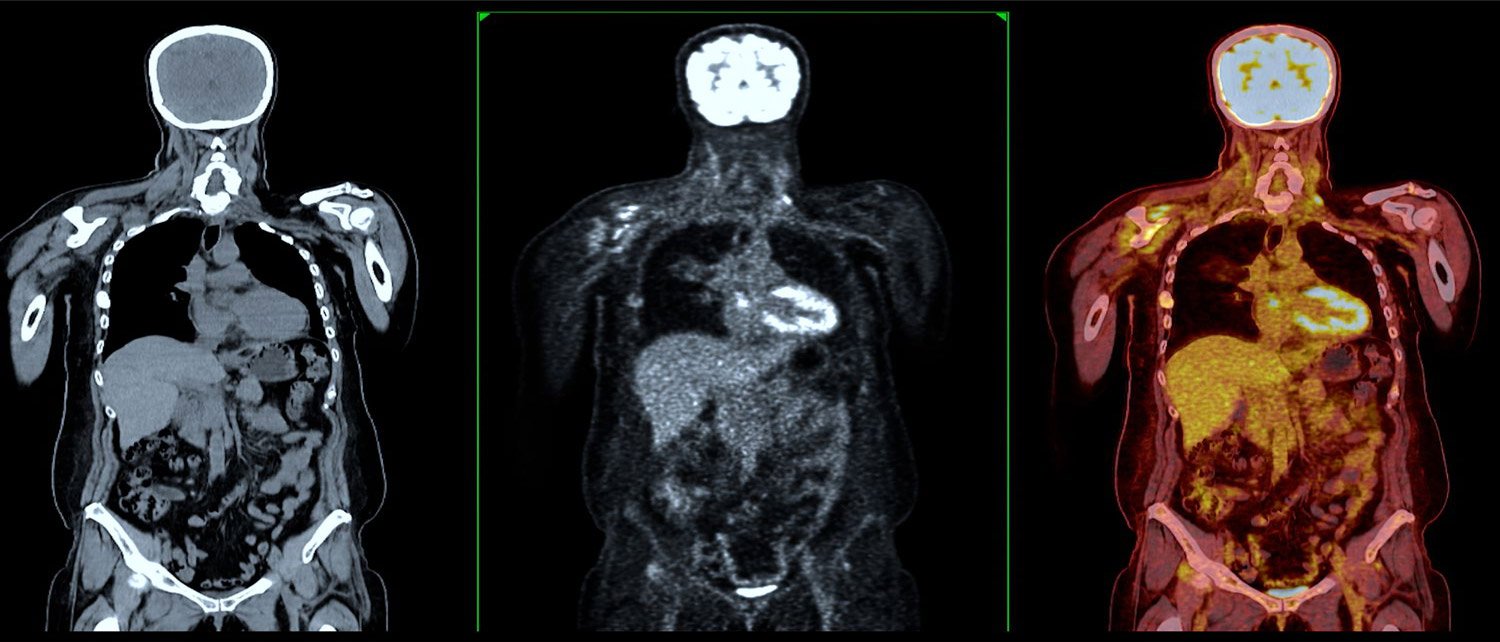

Sample image obtained using a combination of PET and CT imaging technology.

In many centers, nuclear medicine images can be superimposed with computed tomography (CT) or magnetic resonance imaging (MRI) to produce special views, a practice known as image fusion or co-registration. These views allow the information from two different exams to be correlated and interpreted on one image, leading to more precise information and accurate diagnoses. In addition, manufacturers are now making single photon emission computed tomography/computed tomography (SPECT/CT) and positron emission tomography/computed tomography (PET/CT) units that are able to perform both imaging exams at the same time. An emerging imaging technology, but not readily available at this time is PET/MRI.

CT imaging uses special x-ray equipment, and in some cases a contrast material, to produce multiple images or pictures of the inside of the body. These images can then be interpreted by a radiologist on a computer monitor. CT imaging provides excellent anatomic information.

Today, almost all PET scans are performed on instruments that are combined PET and CT scanners. The combined PET/CT scans provide images that pinpoint the anatomic location of abnormal metabolic activity within the body. The combined scans have been shown to provide more accurate diagnoses than the two scans performed separately.